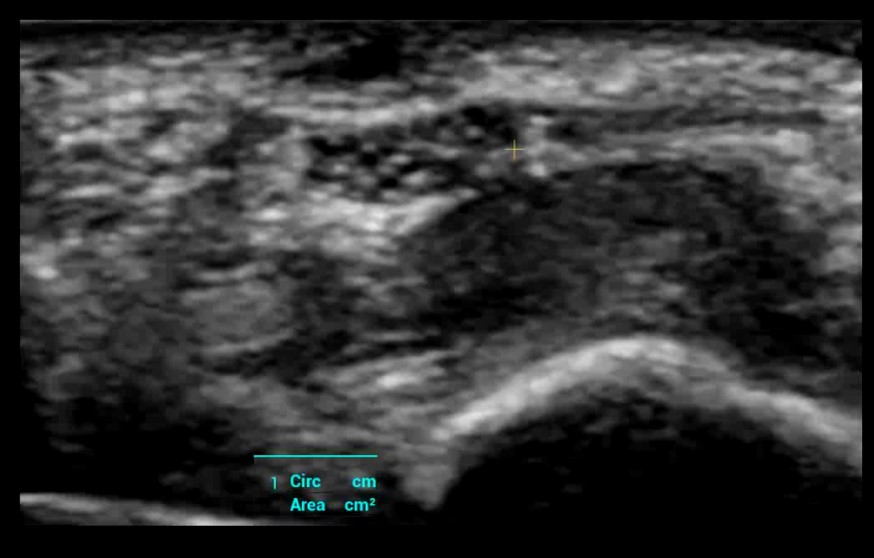

HD-Scope: Zlepšená diagnostika drobných lézií. Zlepšenie detailov a kontrastu vyznačenej oblasti, čo je obzvlášť užitočné pre zobrazenie hraníc a vnútornej štruktúry.

HD-Scope: Zlepšená diagnostika drobných lézií. Zlepšenie detailov a kontrastu vyznačenej oblasti, čo je obzvlášť užitočné pre zobrazenie hraníc a vnútornej štruktúry.

Smart Trace: Automatické a presné ohraničenie lézie a ich pomeranie.

Smart Trace: Automatické a presné ohraničenie lézie a ich pomeranie.